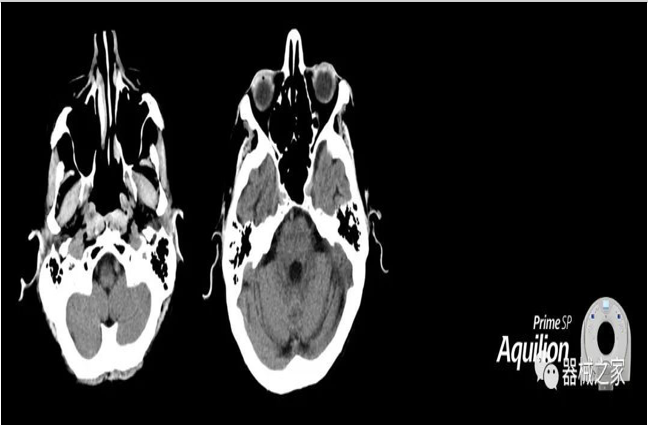

佳能醫(yī)療為Aquilion Prime,Lightning CT系統(tǒng)增加了放射治療套裝

從業(yè)必讀~